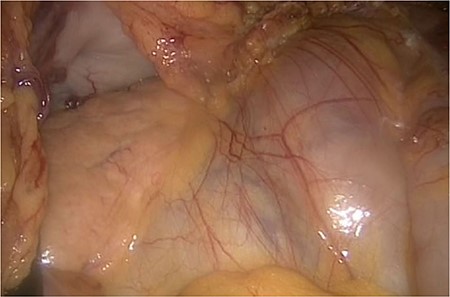

On the left side, we show the retroperitoneal pancreas, with the (as well) retroperitoneal jejunum on the right side.

We accidentally opened the dorsal peritoneum (Fig. 2), and found the small bowel underneath - retroperitoneal (Fig. 3).